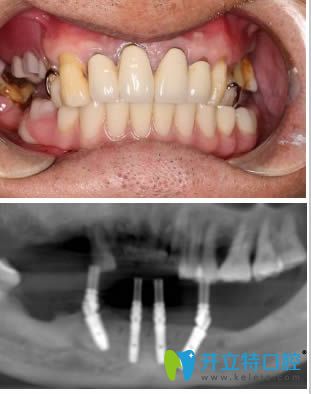

術(shù)后影像及半口即刻種植牙一年后的樣子: